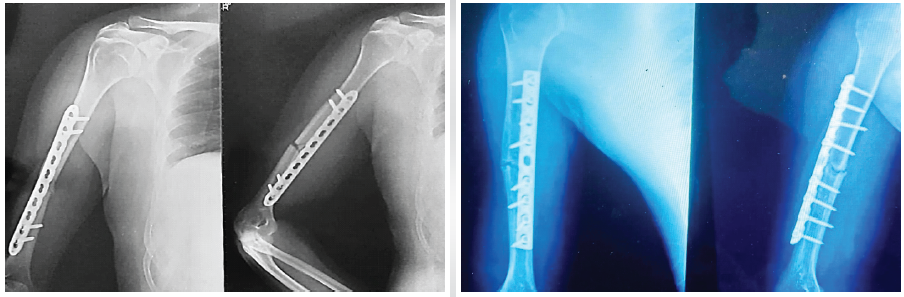

The mean time taken for union was 13.3 ± 3.1 weeks (95% confidence interval [CI]: 10.9–20) in Group A and 18.1 ± 4.7 weeks in Group B (95% CI: 12.1–24), which shows a significant statistical variation (P = 0.03, independent t-test). Both approaches helped in healing the bone, with Group A having a quicker union (Figs. 2A, 2B and 3) [1,2,4,7,15].

Fig. 3: Osseous healing in the ORPO Group: An AP and lateral radiographic images of direct fixation (via a dynamic compression plate) along the posterior cortex of the right humerus, without any discernible fracture line, at 14 weeks post-surgery.